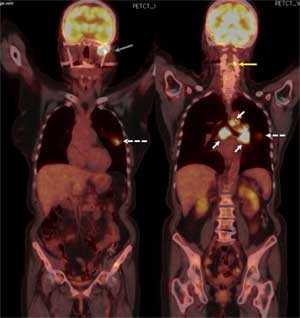

При иммуногистохимическом исследовании было обнаружено, что клетки экспрессируют цитокератин-7. Пробы на CK20, щитовидный фактор транскрипции, нейроэктодермальный антиген S100, чёрную меланому человека-45 и молочных желёз-2 были отрицательны. Индекс пролиферации антител ki67 был около 50%. Данные параметры соответствуют параметрам метастазирующего крупноклеточного рака лёгких. Позитронно-эмиссионная компьютерная томография грудной клетки выявила наличие первичного очага в левом лёгком, а также увеличенные узлы в воротах лёгких и трахеобронхиальные узлы и увеличение метаболической активности в околопозвоночных областях.

Рис. 6. На позитронно-эмиссионной компьютерной томограмме виден первичный очаг раковой опухоли в левом лёгком (показан белой пунктирной стрелкой), трахеобронхиальные узлы и узлы в воротах лёгких (показаны сплошными белыми линиями), грудной паравертебральный метастаз (показан жёлтой стрелкой) и метастаз в мыщелок нижней челюсти слева (показа сероё стрелкой).

Позитронная эмиссионная томография проводится, как правило, после биопсийного подтверждения диагноза метастазирующего рака. Область распространения рака определяется по данным ПЭТ и КТ. В данном случае ПЭТ/КТ позволила ассоциировать множественные костные метастазы с объёмным образованием в лёгких, что, в своё очередь, позволило нам поставить диагноз метастазирующего рака лёгких IV стадии.